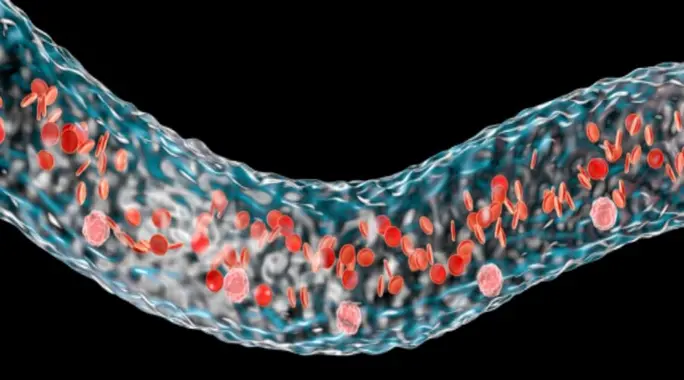

فقر الدم الخبيث، أو ما يُعرف طبيًا باسم Anemia Pernicious، ليس مجرد نقص عادي في فيتامين B12. إنه نوع من فقر الدم يحدث عندما لا يستطيع جسمك امتصاص هذا الفيتامين الحيوي من الأطعمة التي تتناولها. يُعد فيتامين B12 ضروريًا لإنتاج خلايا الدم الحمراء السليمة ولوظائف الجهاز العصبي الطبيعية. بدون كميات كافية منه، قد تواجه مجموعة واسعة من الأعراض التي تؤثر على جودة حياتك.

تنتج هذه الحالة عادةً عن مشكلة في الجهاز الهضمي، حيث يهاجم الجهاز المناعي للجسم خلايا المعدة المسؤولة عن إنتاج بروتين يُسمى “العامل الداخلي” (Intrinsic Factor). هذا العامل حيوي لامتصاص فيتامين B12 في الأمعاء الدقيقة. بدون العامل الداخلي، يمر فيتامين B12 عبر الجهاز الهضمي دون أن يتم استخدامه، مما يؤدي إلى نقصه التدريجي.

لفهم أهمية العلاج، من الضروري معرفة ما يحدث داخل الجسم. يقوم الجهاز الهضمي عادة بإنتاج بروتين يُعرف باسم “العامل الداخلي” في المعدة. هذا العامل يرتبط بفيتامين B12 ويساعد على امتصاصه لاحقًا في الأمعاء الدقيقة.

في حالة فقر الدم الخبيث، يهاجم الجهاز المناعي هذا العامل الداخلي بالخطأ، مما يمنعه من أداء وظيفته. نتيجة لذلك، حتى لو تناولت كميات كافية من فيتامين B12 من الطعام، فإن جسمك لن يتمكن من امتصاصه واستخدامه، مما يؤدي إلى النقص.